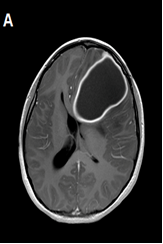

Neuroanesthesia in an Awake Patient in A University Hospital in Latin America

Ana-MaríaOcampo Pérez, Angel-RicardoArenas Villamizar*, Karen-DayanacGonzalez Solarte, Johnnie-SmithHusband Luque

Anesthesia and Medical Practice Journal